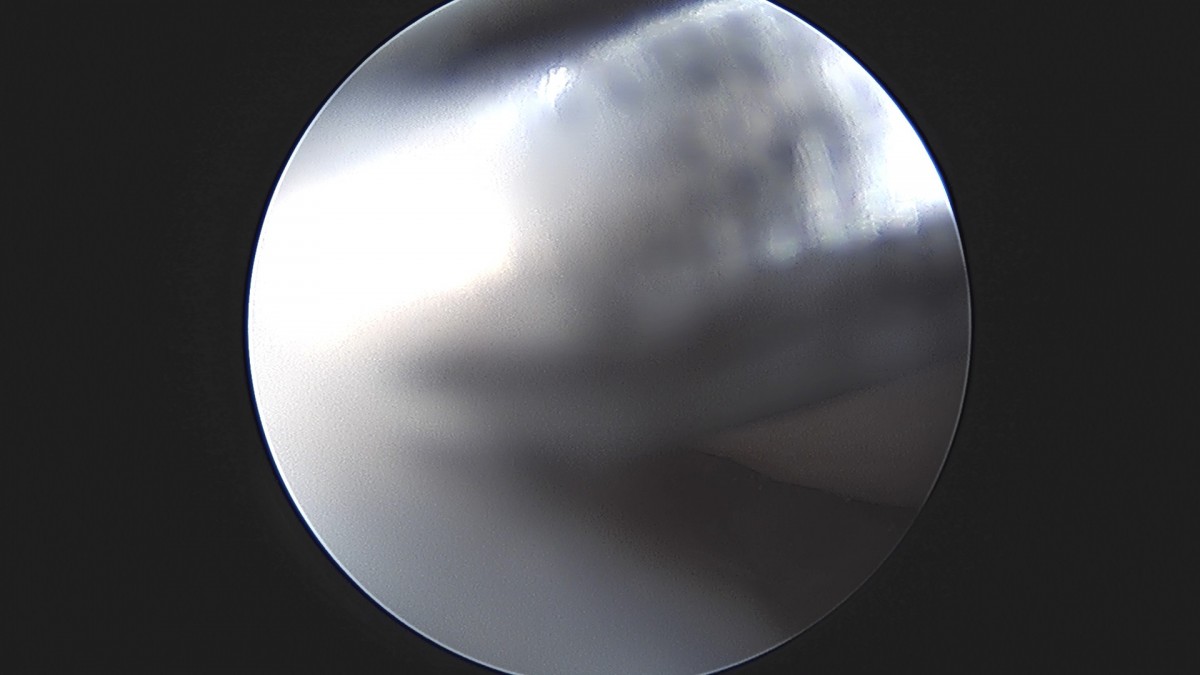

이재상원장님 무릎 반월상 연골판 절제술 최용O 환자

dae765e4d9ac96aee867c9d6292d8784_1758005818_8264.jpg